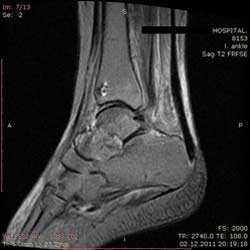

На Т2-ВИ в сагиттальной и корональной плоскостях определяется стресс-перелом дистальных отделов малоберцовой кости.

Рис4. а. на КТ перелом таранной и большеберцовой костей, б. на МРТ перелом таранной кости